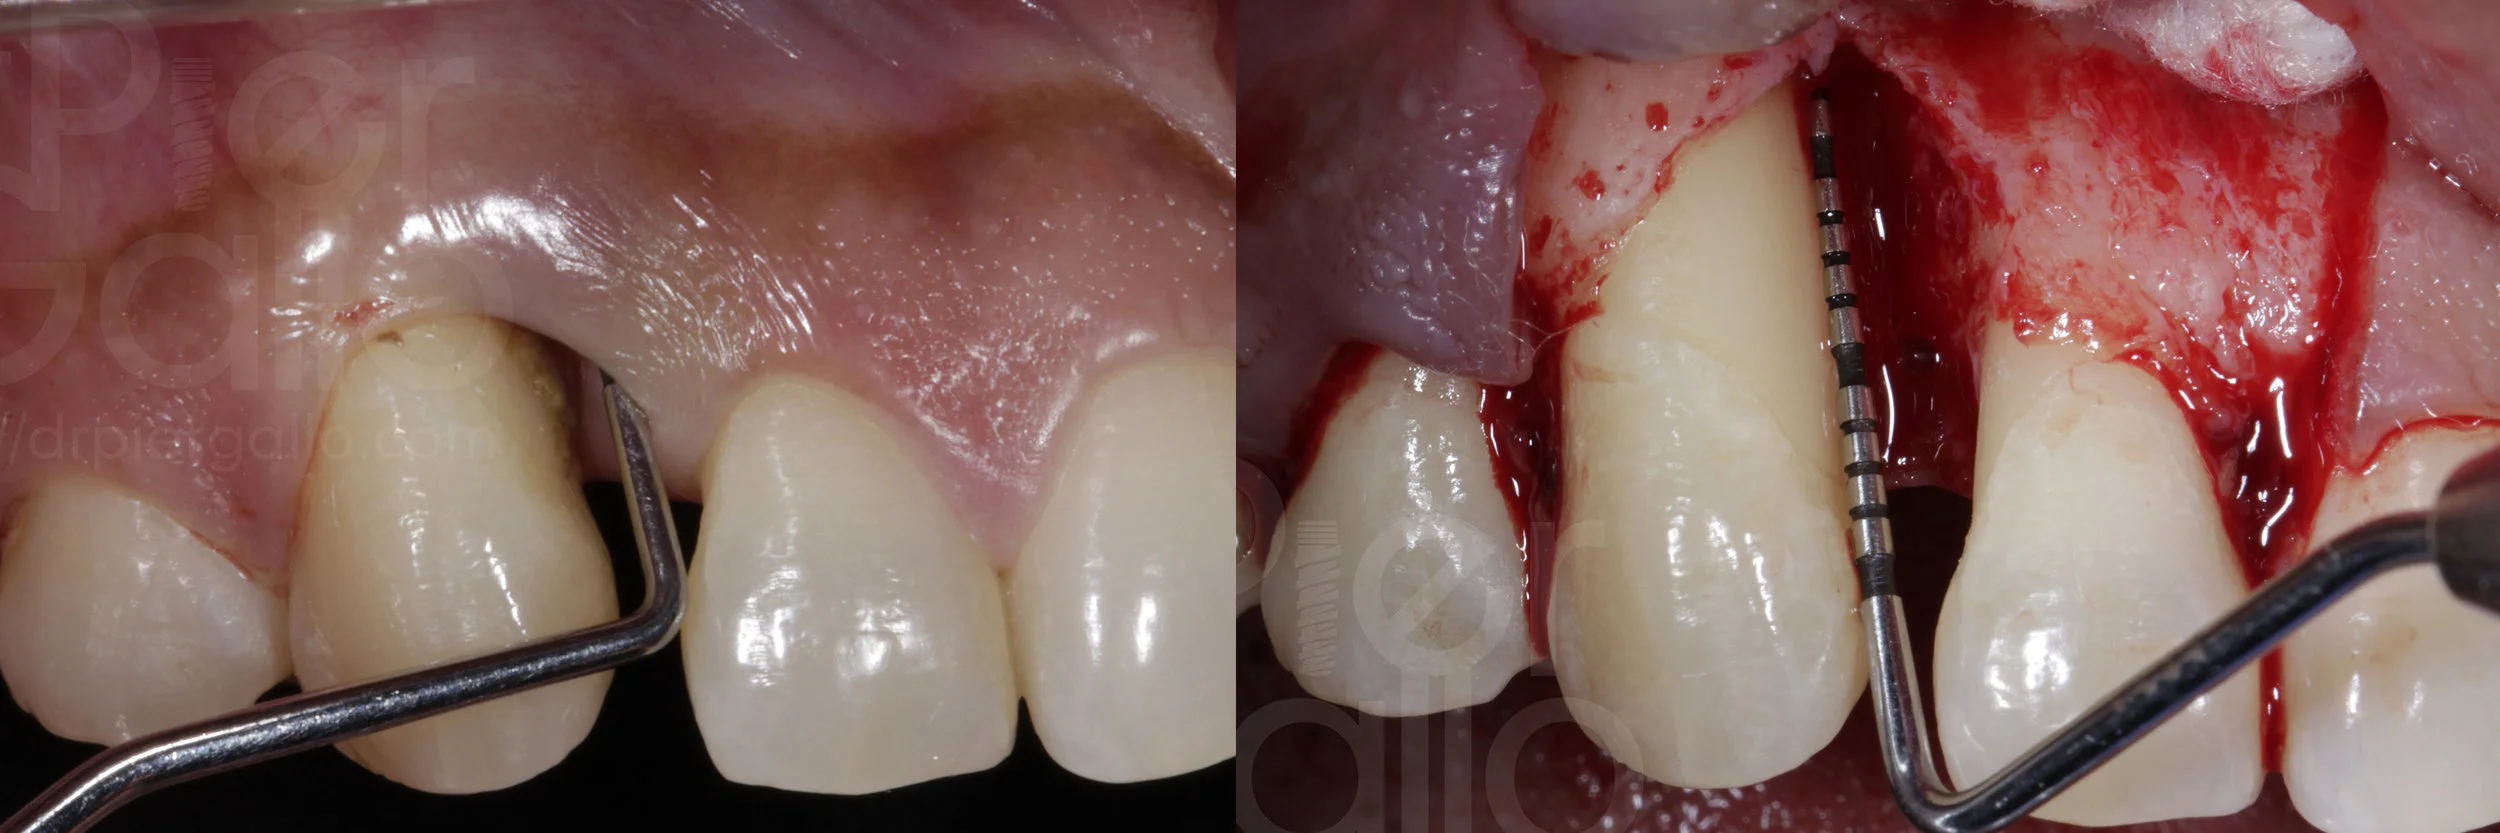

Paciente de 36 años de edad que presenta una pérdida ósea vertical a nivel del 13, con profundidad de bolsa de 15mm, se programa para hacer una Regeneración Tisular Guiada con rhPDGF-BB.

Por ultimo control radiográfico y clínico a los 6 meses, evidencia una ganancia de 10 mm de inserción epitelial alrededor del diente.